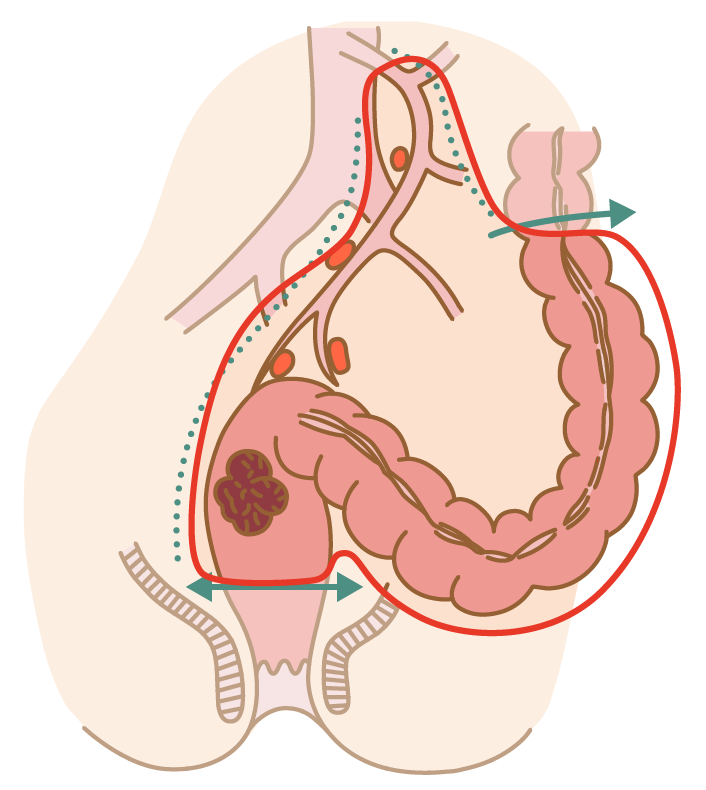

大腸がんの手術について 消化器 一般外科 受診案内 聖路加国際病院

鼠径ヘルニア 脱腸 について 子どもだけじゃない 成人も要注意 かりゆし会の広報誌 あすなろ